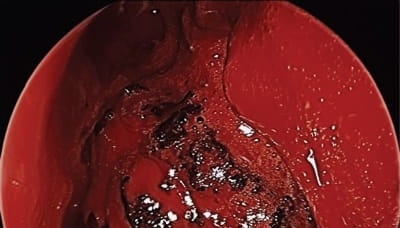

Dr. Rodriguez was presented with such a case in April 2015 – a young man with NF-2 who’d previously had surgery at another hospital to remove one of his bilateral acoustic neuromas. The patient complained of left facial pain and pressure, nasal airway obstruction, decreased sense of smell and epistaxis. Imaging demonstrated a left infratemporal fossa/pterygopalatine fossa mass, consistent with a schwannoma.

“It had remodeled the medial wall of the pterygopalatine fossa and floor of the orbit,” Dr. Rodriguez says. “It had expanded posteriorly to be lateral to the left sphenoid sinus at the base of the temporal lobe.”

To resect the tumor, Dr. Rodriguez and his team opted for an endonasal approach. “Normal endoscopic sinus surgery is all about preserving normal structures,” Dr. Rodriguez says. “The problem is when you’re doing tumor surgery, you need wide access. If you get into bleeding, you can’t be in a limited space especially with vessels like the internal maxillary artery. To gain wide exposure, we did an endoscopic medial maxillectomy approach involving resection of the inferior turbinate, lacrimal bone and medial maxilla to be able to take a 0 degree scope, put it in the nostril, turn it to the side and see the entire back wall of the maxillary sinus straight on.

“When the tumor was grossly resected, the patient’s orbital floor was basically free-floating because of bone loss from compression by the tumor,” Dr. Rodriguez adds. “However, with the periorbita intact, his eye maintained normal position following resection.”

There was no leak of cerebrospinal fluid following surgery, and the internal maxillary artery was identified and was left intact. His pathology was schwannoma, and following recovery, the patient’s symptoms resolved. He did not develop “empty nose syndrome,” which can occur after aggressive endonasal surgery, and he did not develop numbness of V2. However, the patient does have some numbness on the left side of his hard palate.